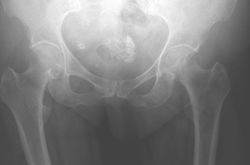

TOTAL HIP REPLACEMENT

Hip replacement is one of the most successful procedures in modern medicine.

A hip joint is made of 2 components - a socket or cup that replaces the native acetabulum and a femoral stem that replaces the femoral head. These can either be fixed to host bone using cement or allowing the patient's bone to grow onto the surface of the implant. We use a variety of implants to suit each patient's anatomy and function profile.

Arthritis

Most symptoms from the hip are due to osteoarthritis. Sometimes there will be a predisposing structural abnormality in the hip due to childhood conditions such as dysplasia of the hip, Perthes disease or slipped upper femoral epiphysis. Other causes of hip arthritis include inflammatory arthritis, infection or trauma.